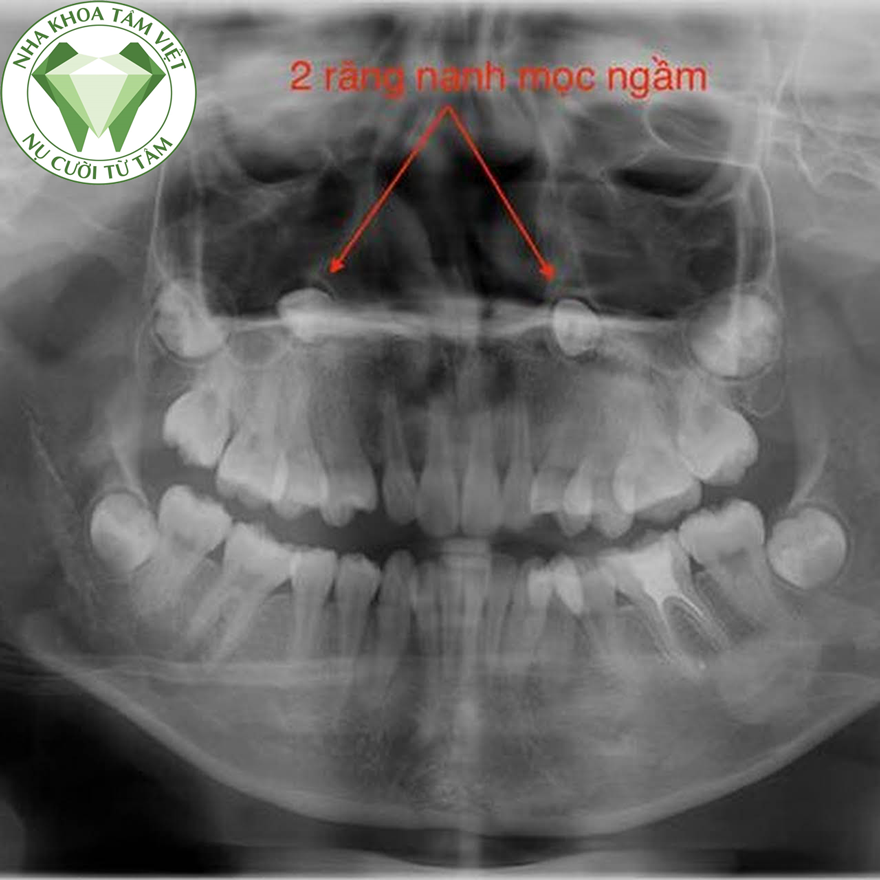

Thông thường, đối với một trung tâm nha khoa uy tín thì chụp X- quang cần được tiến hành trước tiên cùng với các thao tác như chụp cận chóp, phim cắn, phim sọ nghiêng chụp theo kỹ thuật từ xa.. Là những hình ảnh rất cần thiết để đánh giá vị trí của răng nanh, hình dạng và những tác động của răng nanh đối với răng kế cận.

- Để chẩn đoán răng nanh ngầm sẽ dựa vào kết quả khám lâm sàng của bác sĩ và ảnh chụp X quang. Khi khám trong miệng có thể biết được còn hoặc không còn răng nanh sữa nhưng sẽ không thấy răng nanh trưởng thành, mặc dù các răng trưởng thành khác đã mọc, sờ có thể thấy phồng ở trong vòm miệng.

- Khám X quang thông thường như cận chóp, phim cắn, Panorama phim sọ nghiêm chụp theo kỹ thuật từ xa.. là những hình ảnh rất cần thiết để đánh giá vị trí của răng nanh, giúp dự đoán được khả năng mọc và niềng răng, nếu chân răng bị cong sẽ làm cho quá trình niềng răng không thuận lợi.